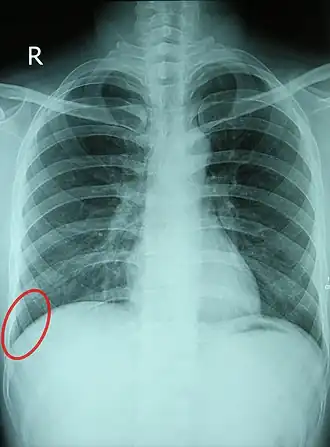

Chest X-ray of a 30-year-old healthy man, with the costodiaphragmatic recess label in red ellipse | |

The costodiaphragmatic recess, also called the costophrenic recess or phrenicocostal sinus,[1] is the posterolateral fringe of the pleural space, a potential space around the lung inside the pleural cavity. It is located at the acutely angled junction ("reflection") between the costal and diaphragmatic parietal pleurae, and is interpreted two-dimensionally on plain X-rays as the costophrenic angle. It measures approximately 5 cm (2.0 in) vertically and extends from the eighth to the tenth rib along the mid-axillary line.

In anatomy, the costophrenic angles are the places where the diaphragm (-phrenic) meets the ribs (costo-).

Each costophrenic angle can normally be seen as on chest x-ray as a sharply-pointed, downward indentation (dark) between each hemi-diaphragm (white) and the adjacent chest wall (white). A small portion of each lung normally reaches into the costophrenic angle. The normal angle usually measures thirty degrees.